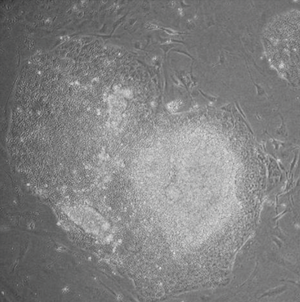

- المورفولوجيا: كانت الخلايا الجذعية المحرضة متعددة القدرات متشابهة مورفولوجياً مع الخلايا الجذعية الجنينية. تميزت كل خلية بشكلها الدائري، ونوية كبيرة، وسيتوپلازم قليل. كما كانت مستعمرات الخلايا الجذعية المحرضة متعددة القدرات مشابهة لمستعمرات الخلايا الجذعية الجنينية. شكلت الخلايا الجذعية المحرضة متعددة القدرات البشرية مستعمرات حادة الحواف، مسطحة، ومتراصة بإحكام، تشبه مستعمرات الخلايا الجذعية الجنينية البشرية، بينما شكلت الخلايا الجذعية المحرضة متعددة القدرات للجرذان مستعمرات مشابهة لمستعمرات الخلايا الجذعية الجنينية للجرذان، أقل تسطحاً وأكثر تكتلاً من مستعمرات الخلايا الجذعية الجنينية البشرية.